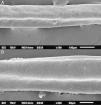

The eyelash examination showed well-developed grooves at medium magnifications (Fig. 1), high magnifications showed cuticle disorganization, in addition to the grooving, and some hair shafts had more than one groove (Fig. 2). Examination of head hairs also revealed grooves (Fig. 3) at small and medium magnifications, less evident than in the eyelashes. High magnifications showed slight cuticle disorganization (Fig. 4).

The ultrastructural findings observed secondary to the use of panitumumab are similar to those previously described for erlotinib and gefitinib, in which grooving was described and classified as pili canaliculi. In the case of erlotinib, eyelash trichomegaly and curly hairs, were seen, ultrastructurally grooves and hair twisting were observed. In the reported case of gefitinib use, the alterations were subclinical with discrete grooving. The case investigated here had important eyelash trichomegaly, with more discreet alterations of head hairs, both clinically and on ultrastructural examination. Panitumumab prolongs the anagen phase, hence the occurrence of trichomegaly, with more evident effects on the eyelashes.